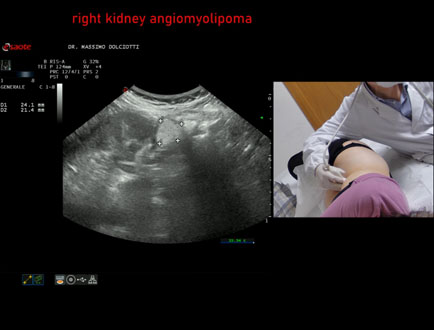

Data inserimento: 03/04/2026

Ecografia del: 12/03/2026

Strumento: Esaote MyLab Eight

Sonda: Convex Multifrequenza 1-8 MHz

Età Paziente: F 66 anni

Motivazione dell'esame: follow up per angiomiolipoma renale destro

Commento all'esame: le immagini ed il video documentano al rene destro, in sede corticale polo inferiore, immagine iperecogena, a margini definiti, delle dimensioni di 25 x 23 mm, senza segni di vascolarizzazione, da ricondurre, come prima ipotesi, ad angiomiolipoma.

Conclusioni: angiomiolipoma del rene destro (angiomyolipoma of the right kidney).

In collaborazione: Dr.ssa Marica Manfredi - Ancona, Dr. Ilir Qose - Ancona

Presentazione: Dr. Massimo Dolciotti - Ancona

Elaborazione digitale: Andrea Dini - Ancona